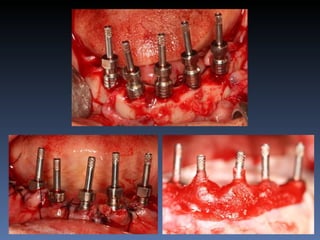

BOX 3

Kátia Maria Cavicchia

Idade – 43 anos

Sexo – Feminino

Raça – Caucasiana

ASA – II

Data- 29-04-2012

Diagnóstico: Desdentado parcial

bilateral posterior da mandíbula.

Plano de tratamento: Reabilitação bilateral posterior

mandibular com instalação de 6 implantes endo-

ósseos, para reabilitação protética fixa.

Zona 4.4, 4.5, 4.6   Zona 3.5, 3.6, 3.7